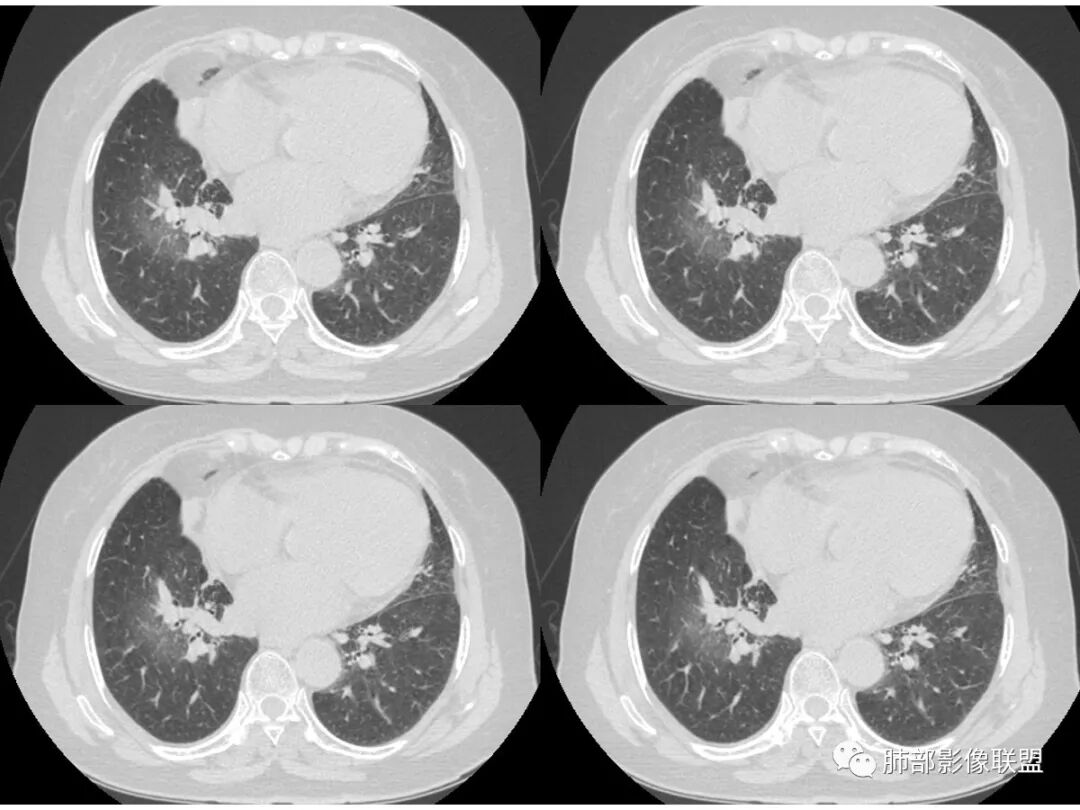

右肺上叶大片状阴影,内见僵硬的支气管,部分支气管轻度扩张,内见一空洞和液平,病灶边缘可见磨玻璃影,首先考虑恶性病变,粘液性腺癌伴感染可能。

老年女性,右肺上叶大片实变及磨玻璃密度影,磨玻璃边缘清晰,内可见小叶间隔增厚,内可见空洞,似可见分隔,叶间裂局部膨隆,纵膈窗,没有增强,枯树枝不明显,肺炎型肺癌可能,鉴别大叶性肺炎,结核?

老年女性,右肺中上叶病灶,血象不高,血沉高,TB dna阴性,上叶尖端病灶,紧贴胸膜,边界似清非清,中间可见实变,内见枯树枝征,首先考虑粘液腺癌可能性大。患者右肺中叶见空洞、气液平,病灶没多发空洞,可见气液平,考虑合并TB感染。

老年女性,无诱因咳嗽咳痰,白色粘液痰,抗炎治疗无好转,右肺多叶磨玻璃影,其内见枯树枝征,磨玻璃边界清,中间见实变影,且部分实变影内见空洞或局部支气管扩张,内壁光整,无纵隔淋巴结肿大,常规考虑粘液性腺癌,感染性病变待排,细菌性的排除,白细胞不高,不太支持,建议支气管镜检。

1.右上肺大片状影,周围有磨玻璃影,支气管截断征、枯枝征、远端支气管充气征,可见多个大小不等囊泡(支气管阻塞活瓣作用形成),病灶有少许收缩力感,叶间裂被稍牵拉内移;

病史老年女,白痰;影像实变,ggo多数边界清,病灶下缘部分不清,枯树枝,支气管近端阻塞、僵硬,病灶跨叶;病灶内空洞,有液平;间质增厚有结节感;肺炎型肺癌大于干酪性肺炎。

老年女性,咳白粘液痰;右肺上叶大片实变加GGO,局部膨隆也有收缩,见枯树枝征及坏死,考虑恶性~粘液腺癌,鉴别感染,血象不高。

患者老年女性,亚急性起病,胸部CT:右肺上叶大片实变,可内见坏死性空洞,可见mGGO,GGO边缘清晰,局部彭隆,内见支气管充气征,可惜没增强,粘液腺癌要考虑,但病灶明显是内朝外不支持,综合考虑结核,建议查痰找抗酸杆菌、气管镜

老年女性,咳白色粘液痰,右肺跨叶大片高密度影,密度不均匀,其内见支气管枯树征,有空洞,边缘部分清楚,叶间裂有下坠膨隆感。考虑粘液腺癌,鉴别干酪性肺炎